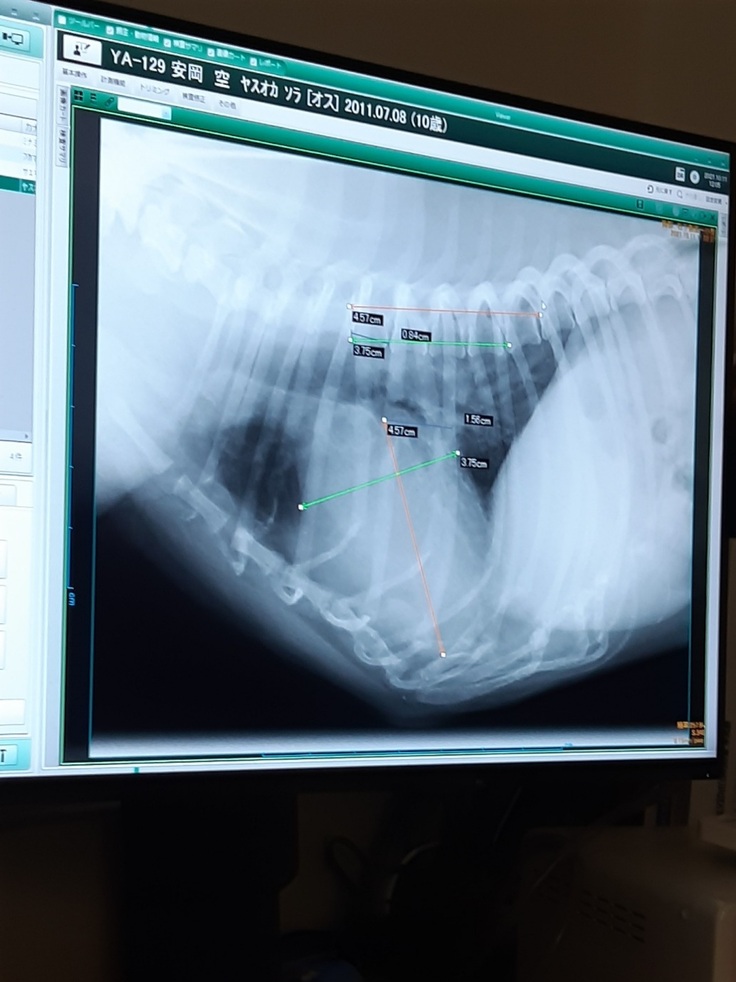

4月11日の僧帽弁閉鎖不全症の弁の形成手術から早いもので今日で半年となります。

今日は半年検診に行って来ました。

今日も心臓検査では、弁の状態が凄くいいと先生から言われました!

この先他の病気で亡くなることがあっても、この心臓病で亡くなることはないと!心臓は寿命まで大丈夫だろうと!

レントゲン検査では、やっぱり気管支が虚脱ぎみかな?と言われました。